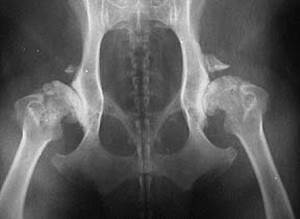

Дисплазия тазобедренного сустава (дисплазия ТБС) – врожденная патология развития тазобедренного сустава, потенциально (однако с высокой степенью вероятности) приводящая по мере взросления животного к серьезным проблемам с

Тазобедренный сустав – простой, многоосный. Состоит из бедренной кости и вертлужной впадины, которую, в свою очередь, образуют три тазовые кости, дополнительно сустав фиксируется круглой связкой. На тазобедренный сустав приходится основной вес как при движении животного, так и в состоянии покоя, что относит к группе риска все крупные и гигантские породы.

Дисплазия определяется рядом разнообразных нарушений в развитии:

- неконгруэнтность суставных поверхностей;

- недоразвитая (чаще всего уплощенная) вертлужная впадина;

Генетические нарушения строения могут быть не только одной конкретной разновидности, но и несколько одновременно, накладывающихся друг на друга. По наиболее часто используемой схеме все имеющиеся отклонения суммируются, и по сумме баллов определяется степень дисплазии. Наиболее часто применяется шкала из 7 стадий дисплазии, определяющих пригодность производителя (оценка проводится в возрасте 12 – 18 месяцев):